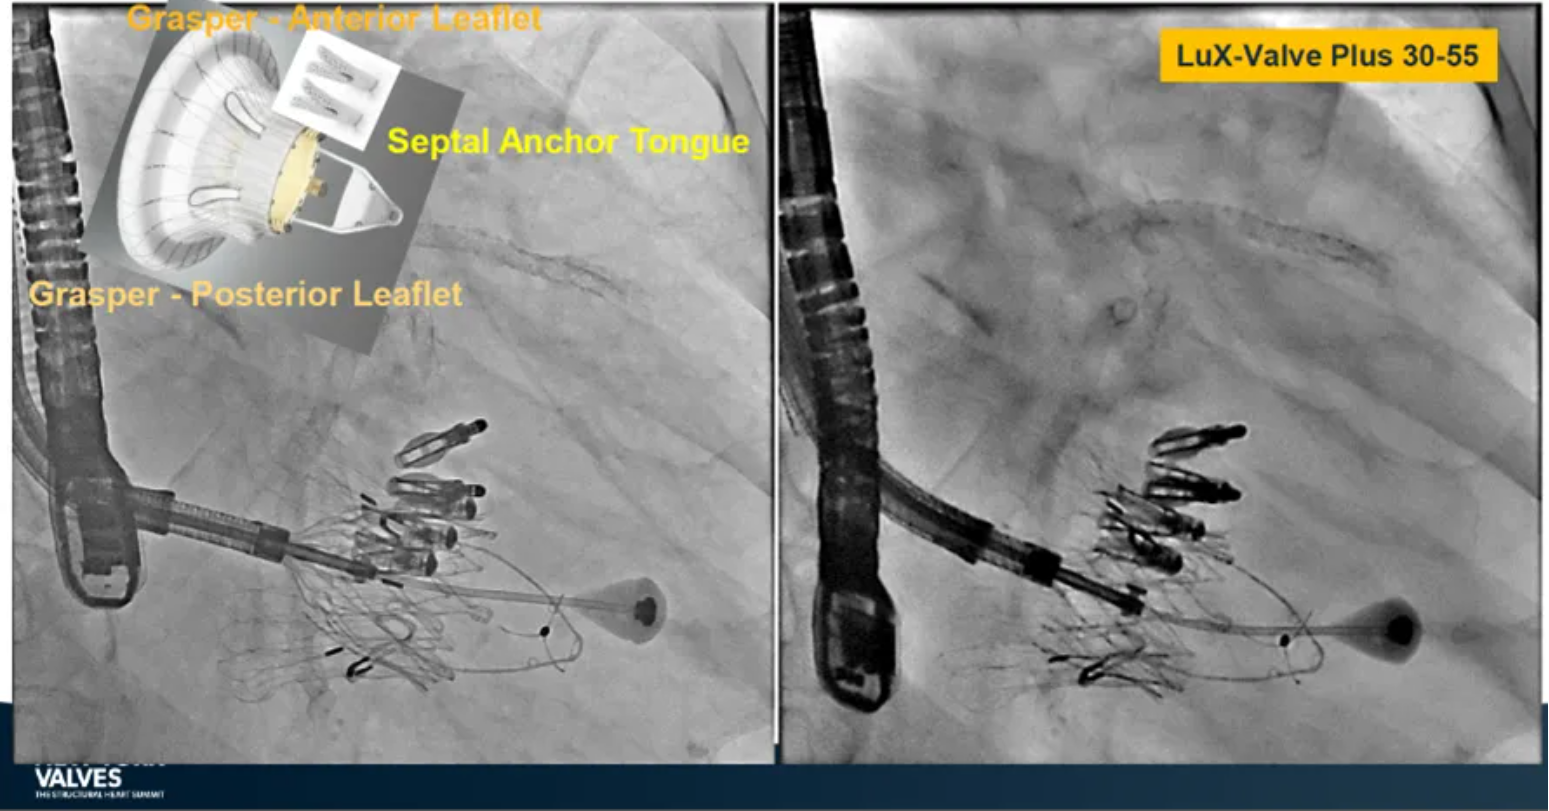

LuX-Valve Plus是健世科技(Jenscare,9877.HK)推出的全新一代經(jīng)頸靜脈三尖瓣置換系統(tǒng)(Transjugular Tricuspid Valve Replacement System),其創(chuàng)新性地采用頸靜脈作為手術入路,在不依賴徑向支撐力的情況下借助室間隔錨定、瓣葉夾持技術構成其多重錨定結構,并通過自適應編織環(huán)有效進行心房側封堵,呈現(xiàn)更好的安全性和有效性。

早在今年5月舉辦的2024歐洲介入心臟病學大會(EuroPCR 2024)上,來自德國慕尼黑路德維希·馬克西米利安大學醫(yī)院(Klinikum der Ludwig-Maximilians-Universität München, Munich, Germany)的Jörg Hausleiter教授公布了在全球多中心開展的同情救治使用經(jīng)驗。在2024年紐約瓣膜會上,Hausleiter教授再次提及LuX-Valve Plus,并介紹到對于無法采用TEER術式的患者也是適用的,例如瓣口接合有較大缺陷和超大瓣環(huán)的患者,以及超聲影像質量較低不適合夾子術式等情況。此外,LuX-Valve Plus能夠擴大治療方式的選擇,尤其是對于超大解剖結構的患者來說,并且展示了優(yōu)異的早期結果。目前,以獲得CE認證為目標的臨床試驗正在歐洲持續(xù)展開。